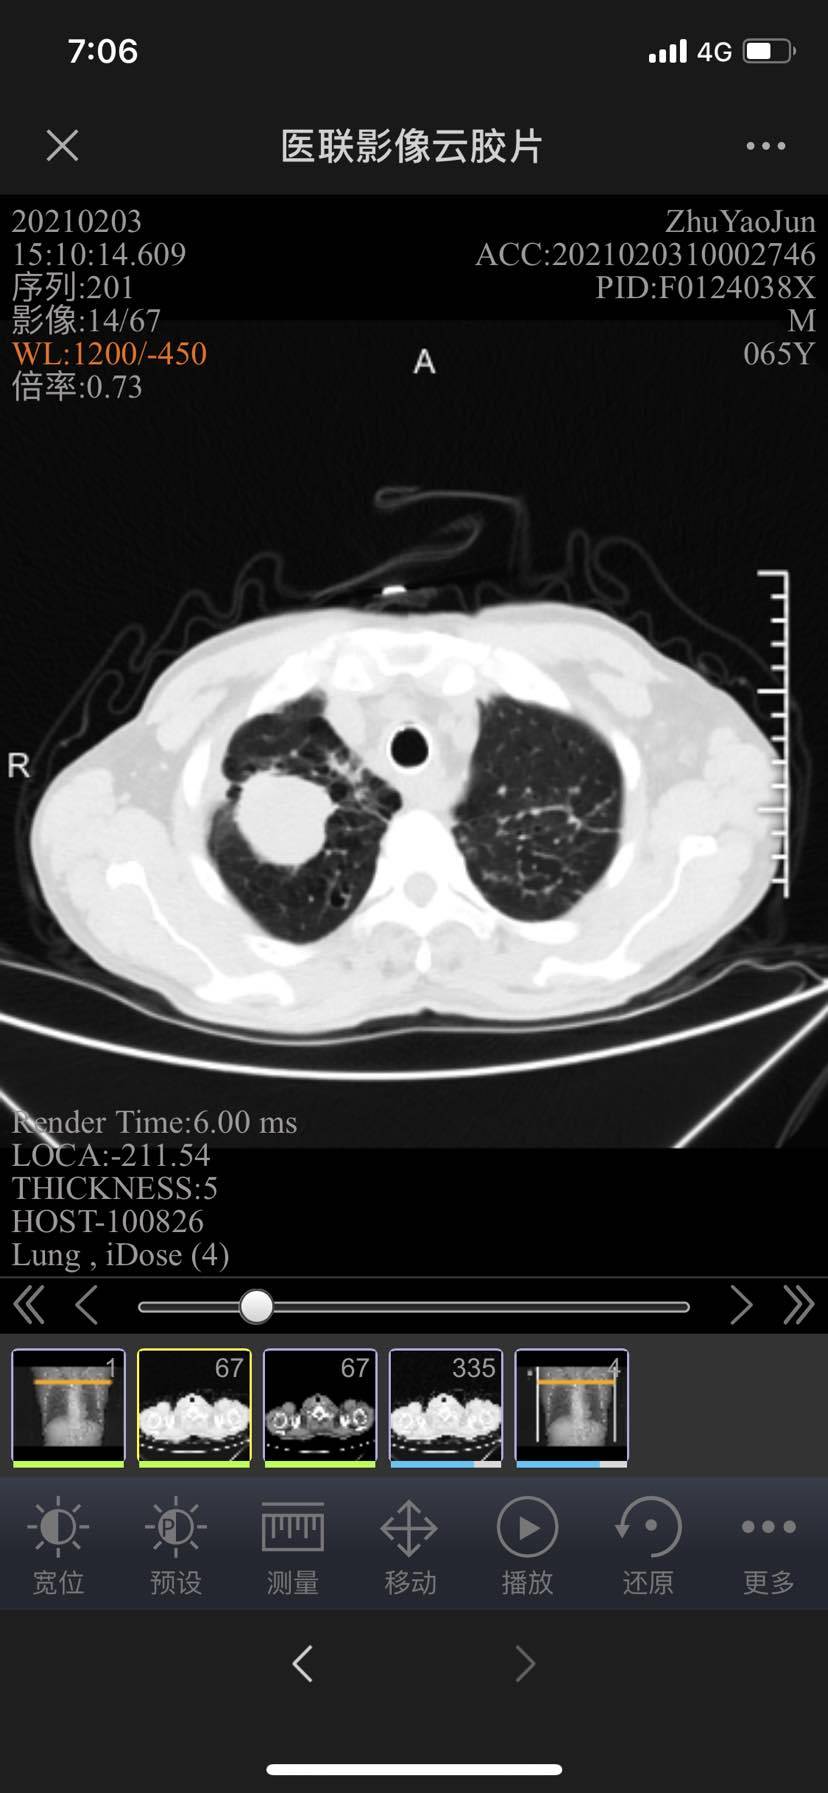

庆幸这次的年终考总算取得了一个阶段性的小胜利,ct显示纵隔内部分淋巴结缩小,自己认真对比了片子确实是肉眼可见的明显缩小了,最让我担惊受怕的气管压迫缓解不少!

2/3新片